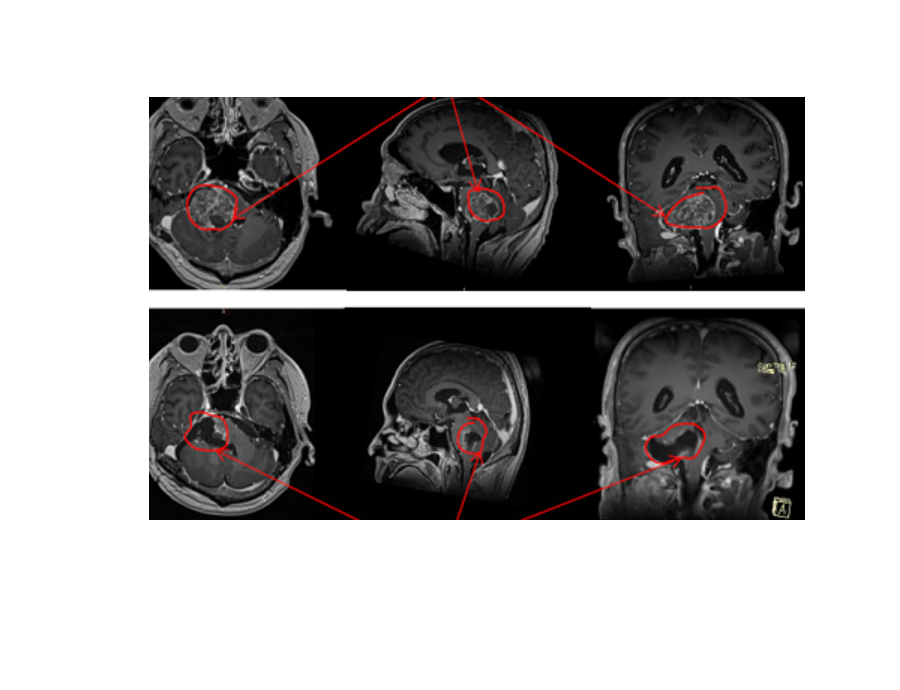

即使如刘女士的IV级弥漫性中线脑干胶质瘤,恶性程度较高,生长速度较快,预后也较差。在国内经过一次治疗再复发后,被国内医生告知,二次手术风险较大,建议放化疗保守治疗。但在德国汉诺威国际神经科学研究所(INI)神经外科主任、国际颅底肿瘤手术教授巴特朗菲教授细致、高超的手术下,再结合INI术中核磁、神经导航等前沿设备,较终还是为较终切除了95%以上的脑干胶质瘤,为保护大脑正常功能,与脑干关系密切的残余部分采取保留,很大水平延长了患者寿命。

刘女士胶质瘤手术影像图: